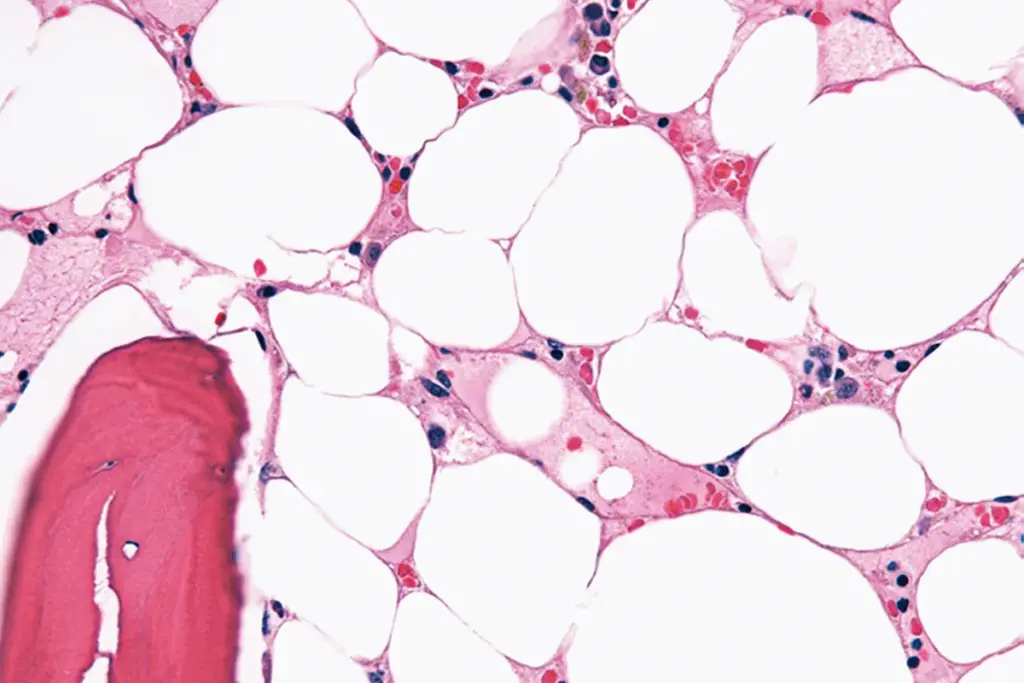

Bone Marrow Biopsy and Definitive Diagnosis

A bone marrow biopsy is key to confirm aplastic anemia. It involves:

- Aspiration: Taking out bone marrow fluid.

- Biopsy: Taking a small bone marrow tissue piece.

The samples are checked for cell count, shape, and genetic issues. In aplastic anemia, the bone marrow has fewer cells, showing it can’t make enough blood cells.